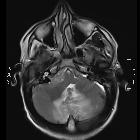

Cerebellar

abscess secondary to occipital dermoid cyst with dermal sinus. Axial T2W image, lesion in midline in vermis region perilesional oedema and mass effect over 4th ventricle with hydrocephalus. Dermal sinus tract through occipital bone defect to scalp dermoid with secondary infection.

abscess secondary to occipital dermoid cyst with dermal sinus. Axial T2W image, lesion in midline with perilesional oedema and mass effect. Communication/dermal sinus tract through occipital bone defect to scalp dermoid with secondary infection. Incidental detected right sided acoustic schwannoma.